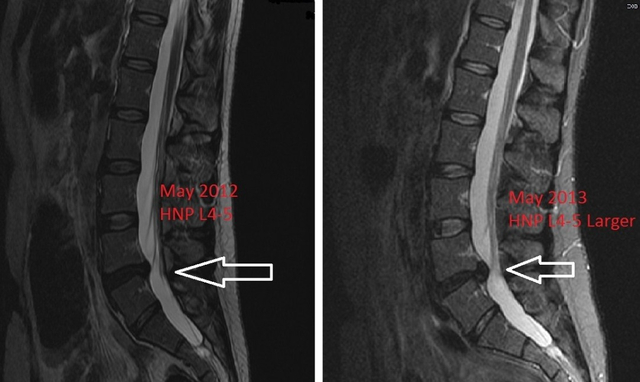

Dalam dunia medis dikenal kode ICD 10 HNP sebagai diagnosis untuk penyakit Hernia Nukleus Pulposus atau Herniated disc. Penyakit ini terjadi akibat salah satu bantalan tulang belakang keluar dan menonjol, sehingga menekan bagian sarafnya.

Di Indonesia, HNP lebih dikenal dengan sebutan saraf kejepit. Umumnya, penyakit ini dapat menimbulkan gejala berupa rasa nyeri, mati rasa, dan kelemahan pada lengan atau kaki pasien.